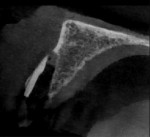

On the day of surgery, the patient presented, and the treatment plan was reviewed. The patient's questions were answered, and informed consent for PET and implant placement was acquired. Preoperatively, 2,000 mg of amoxicillin and 400 mg of ibuprofen were administered to the patient, and he was instructed to swish with chlorhexidine for 1 minute. After a topical anesthetic (20% benzocaine) was applied to the buccal vestibule at the right lateral incisor site with a cotton swab, local anesthesia was administered via infiltration using 1 cartridge of prilocaine (4% Citanest® Plain, Dentsply Sirona) and 2 cartridges of articaine HCL 4% and epinephrine 1:100,000 (Septocaine®, Septodont). Once profound anesthesia was achieved, a surgical carbide bur (P.E.T. Partial Extraction Therapy Bur Kit, Salvin Dental) was used in a highspeed handpiece to make a cut across the center of the maxillary right lateral incisor from the mesial aspect to the distal aspect, sectioning it into facial and lingual halves (Figure 11). Next, an elevator was utilized in the lingual periodontal ligament space to luxate the lingual portion of the root and remove it atraumatically. The facial portion of the root was then shaved from the prior cut at the center until only a 1-mm thick root segment remained that extended approximately 9 mm apically to the crestal bone (Figure 12). A periapical radiograph and a small field of view CBCT image were acquired to verify the integrity of the socket, its facial wall, and the remaining root segment (Figure 13 through Figure 15).